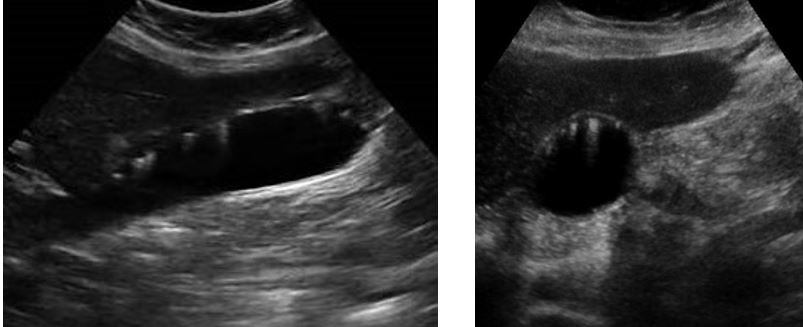

different patterns of cholelithiasis

what is this showing

Cholelithiasis w Floating Stones

Cholelithiasis showing multiple small floating and

nonfloating gallstones

Wall Echo Shadow “WES” Sign